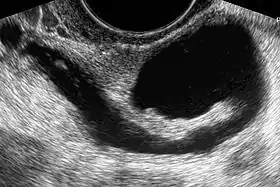

| The presence of a hydrosalpinx by sonography indicates distal tubal obstruction | |

While a full testing of tubal functions in patients with infertility is not possible, testing of tubal patency is feasible. A hysterosalpingogram will demonstrate that tubes are open when the radioopaque dye spills into the abdominal cavity. Sonography can demonstrate tubal abnormalities such as a hydrosalpinx indicative of tubal occlusion. During surgery, typically laparoscopy, the status of the tubes can be inspected and a dye such as methylene blue can be injected in a process termed chromotubation into the uterus and shown to pass through the tubes when the cervix is occluded. Laparoscopic chromotubation has been described as the gold standard of tubal evaluation.[3] As tubal disease is often related to Chlamydia infection, testing for Chlamydia antibodies has become a cost-effective screening device for tubal pathology.[3]